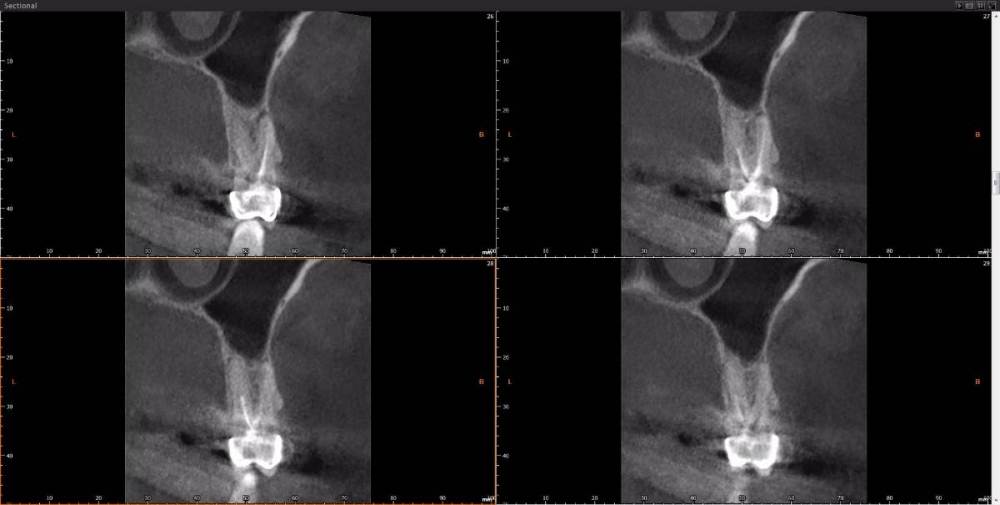

Dude Опубликовано 1 апреля, 2021 Автор Поделиться Опубликовано 1 апреля, 2021 https://disk.yandex.ru/d/6d0pmZ1zArn1Og Так? Ссылка на комментарий